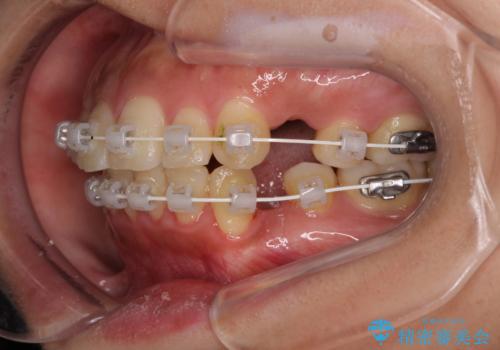

- 前歯のデコボコと口元の突出感を気にして来院された患者様です。

上下前歯がくちばしのように突出していたため、上下左右の第一小臼歯4本を抜歯し、ワイヤー装置にて矯正治療を行うこととしました。

口元の突出感が改善されてことで、下唇に引っかかっていた上顎前歯も気にならなくなりました。